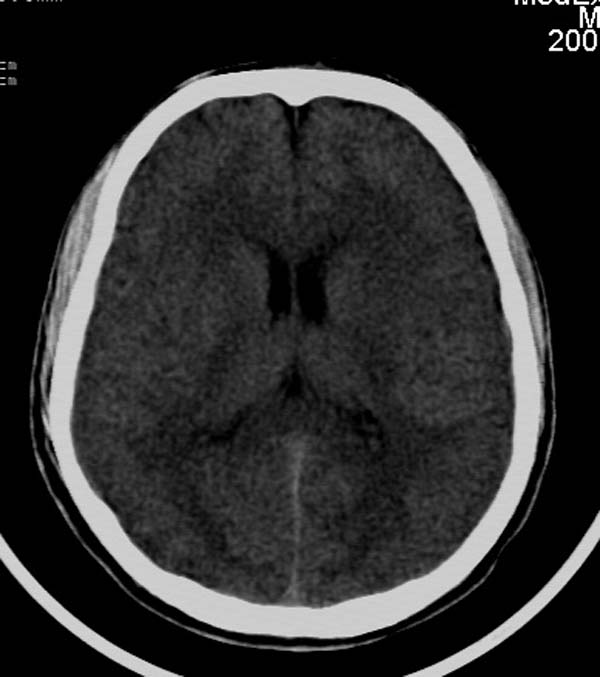

患者,男,24岁。头面部外伤后意识障碍1小时。

小脑幕缘密度增高,考虑有少量出血,建议复查

考虑右侧天幕缘少量蛛网膜下腔出血;建议:必要时复查。

支持少量蛛网膜下腔出血,建议复查.

1)考虑少量蛛网膜下腔出血;建议:必要时复查。2)桥前池及左侧环池表皮样囊肿可能。建议:行mri检查。

考虑右侧天幕缘区域少量蛛网膜下腔出血。